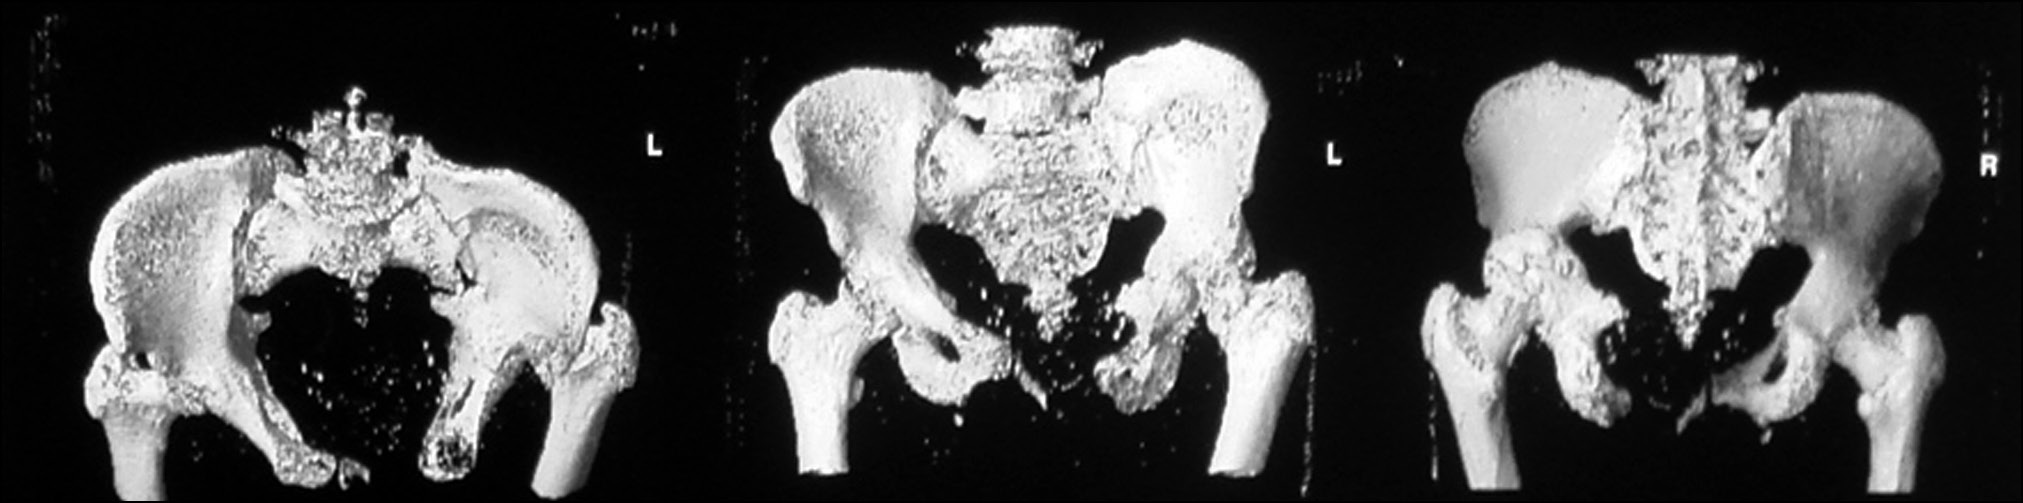

Пациентке проведена компьютерная томография таза (рис. 5).

Рис. 5. Компьютерная томография таза

Fig. 5. Computed tomography of the pelvis